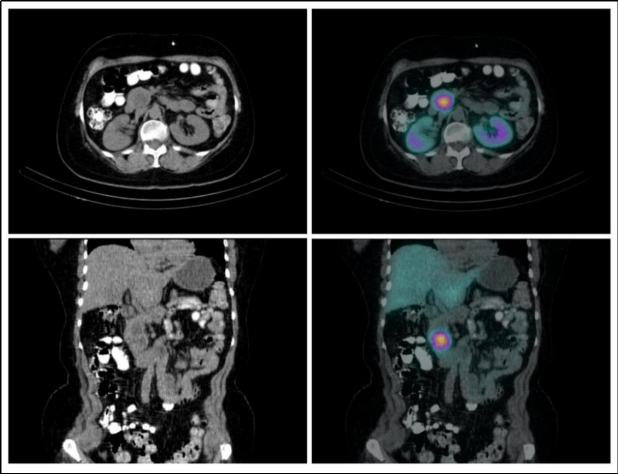

En las imágenes planares se observan múltiples áreas de captación anormal en la fosa posterior y en el aspecto lateral del hilio renal derecho (fig. 1). Se identifican tres lesiones cerebelosas con componente sólido realzante y quístico, altamente vascularizadas, que presentan aumento de perfusión y generan edema extenso obliterando el cuarto ventrículo, consistentes con hemangioblastomas (fig. 2). Existe otra lesión que genera invasión ósea de la mastoides con compromiso del oído interno; en la RM es isointensa e hiperintensa en las secuencias T1, hiperintensa en las secuencias T2, con captación del medio de contraste, por tumor del saco endolinfático (fig. 2). En la valoración de la cavidad abdominal se detecta una lesión sólida en la cabeza/proceso uncinado del páncreas, hipodensa respecto al resto del parénquima, compatible con tumor neuroendocrino (fig. 3).